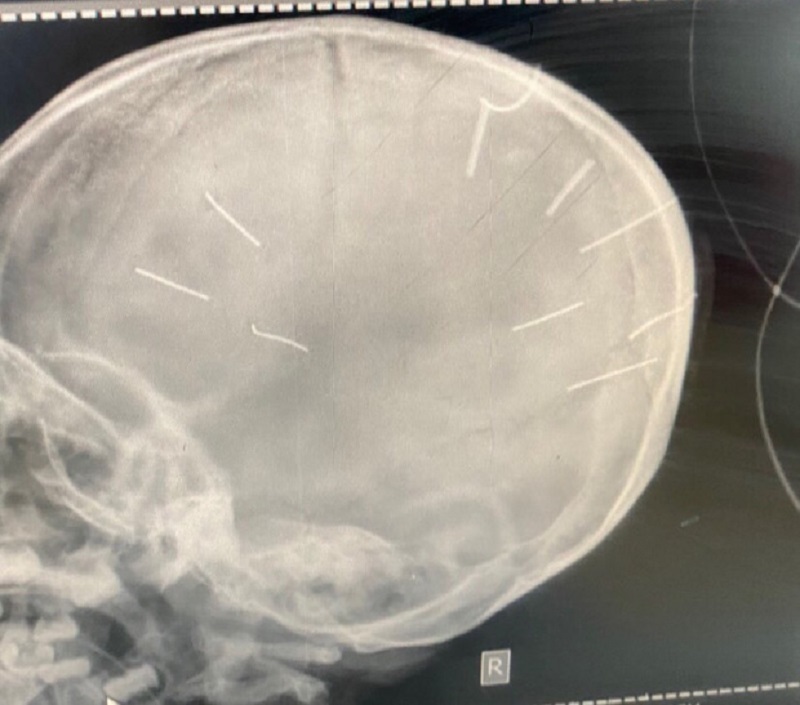

Hình chụp cắt lớp phát hiện hình ảnh giống đinh trong sọ

Ngay sau đó, các bác sĩ khoa cấp cứu đã chụp phim, làm chẩn đoán và phát hiện 9 dị vật giống đinh trong sọ não bé gái nên đã chuyển tuyến lên Bệnh viện đa khoa Xanh Pôn, đồng thời báo Công an huyện Thạch Thất.

Sau khi Bệnh viện Đa khoa Xanh Pôn tiến hành chụp cắt lớp, dựng hình đã nhận thấy có những hình ảnh giống như đinh gỗ ở sọ và tổ chức não của bé Đ.N.A.